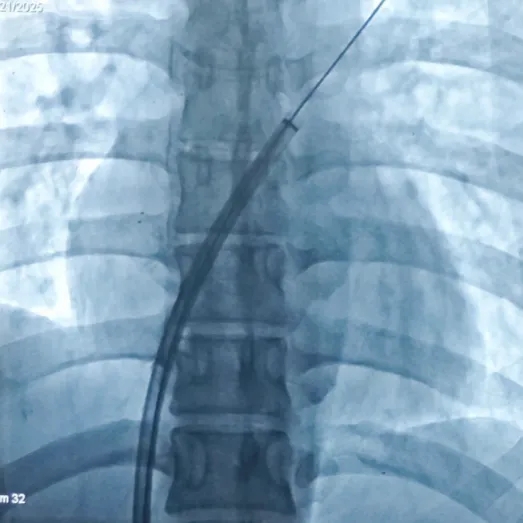

左盘展开

DSA下,左盘面3个Mark点聚拢

超声下左盘贴壁